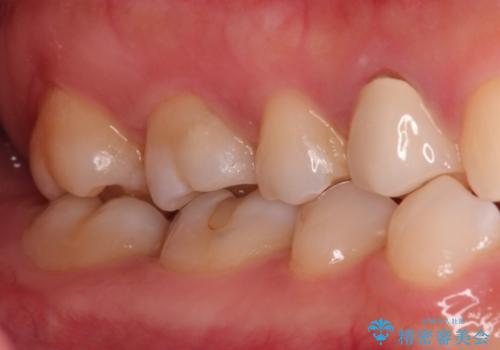

【VPT(歯髄温存療法)とセラミックインレー】深い虫歯でも神経を残したい

- 虫歯が大きく神経まで達していたので、VPT(歯髄温存療法)を行って細菌感染した部分の神経のみ取り除き、保存可能な神経は保存し被せ物はセラミックインレーで治療を行いました。

昔の歯科医療では神経まで虫歯が達している場合は神経を全て取らなければいけませんでした。しかし現代の歯科医療ではBio-C SealerやMTAセメントの開発により健康な神経を残せるようになりました。